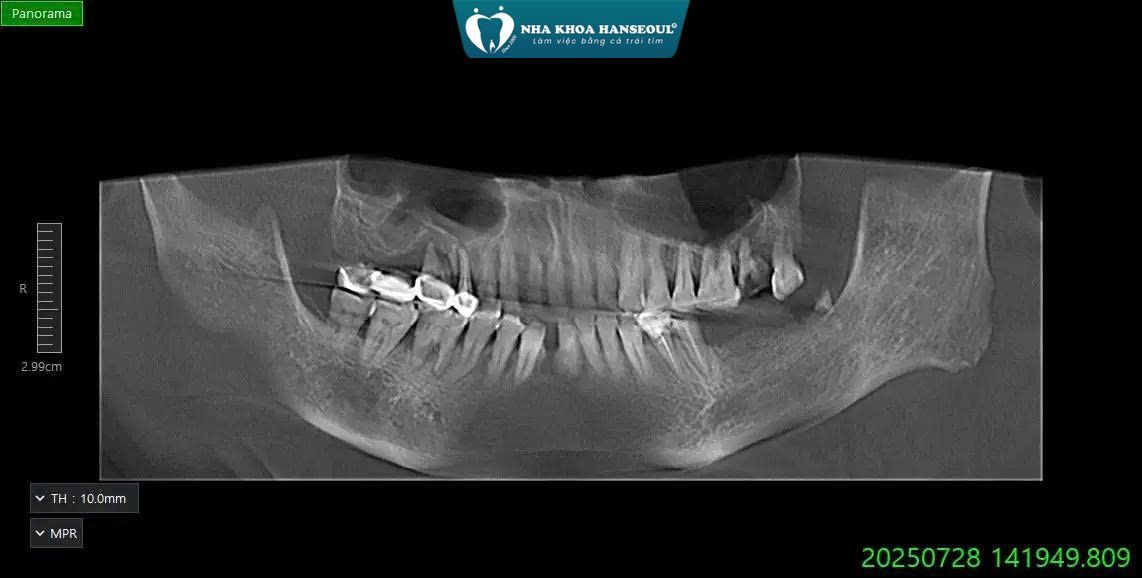

Qua thăm khám lâm sàng, chụp CT ConeBeam và đánh giá sức khỏe răng miệng tổng quát, bác sĩ ghi nhận:

- R27: Răng sâu – viêm nặng, buộc phải nhổ bảo tồn mô → nhổ

- R41: Răng lung lay độ 3 do tiêu xương → nhổ

- R38: Còn chân răng, viêm kéo dài → nhổ chân răng

- Vùng hàm dưới bên trái: R36 – R37 mất răng, tiêu xương mức trung bình → cần phục hồi bằng Implant